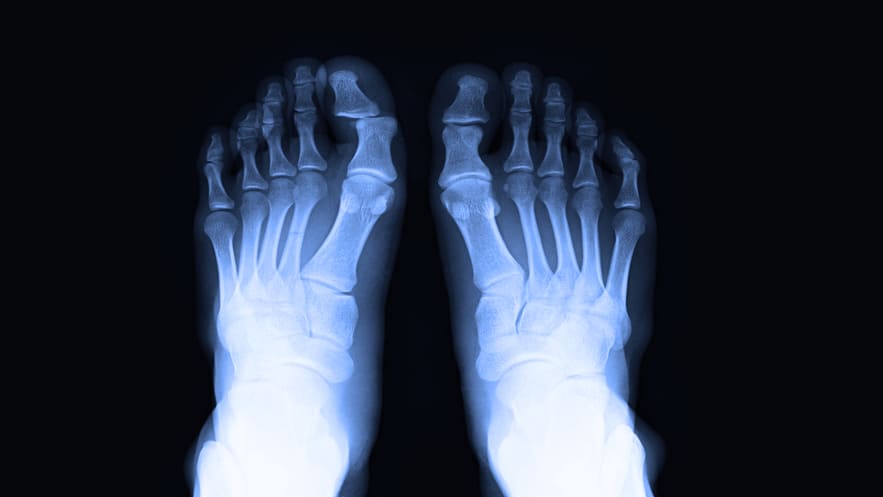

Корригирующая остеотомия стопы

Корригирующая остеотомия стопы целесообразна в следующих случаях:

- подтвержденная вальгусная деформация (Халюс Вальгус) с наличием солевых отложений и костного нароста;